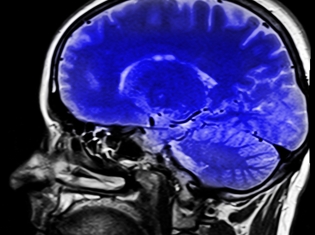

In some patients, tPA can cause deadly bleeding in the brain. Using a new imaging technique, doctors may now be able to identify stroke patients most likely to benefit from tPA and those most likely to sustain damage to the brain.

Richard Leigh, MD, an assistant professor of neurology and radiology at the Johns Hopkins University School of Medicine in Baltimore, Maryland, led this investigation on the use of MRI scanning to evaluate harm to the blood-brain barrier and predict potential bleeding in the brain.

Dr. Leigh and his team looked at MRI scans of 75 stroke patients and assessed how much gadolinium leaked into the brain tissue from surrounding blood vessels during an MRI. Gandolinium is the contrast material injected into a patient to perform an MRI scan.